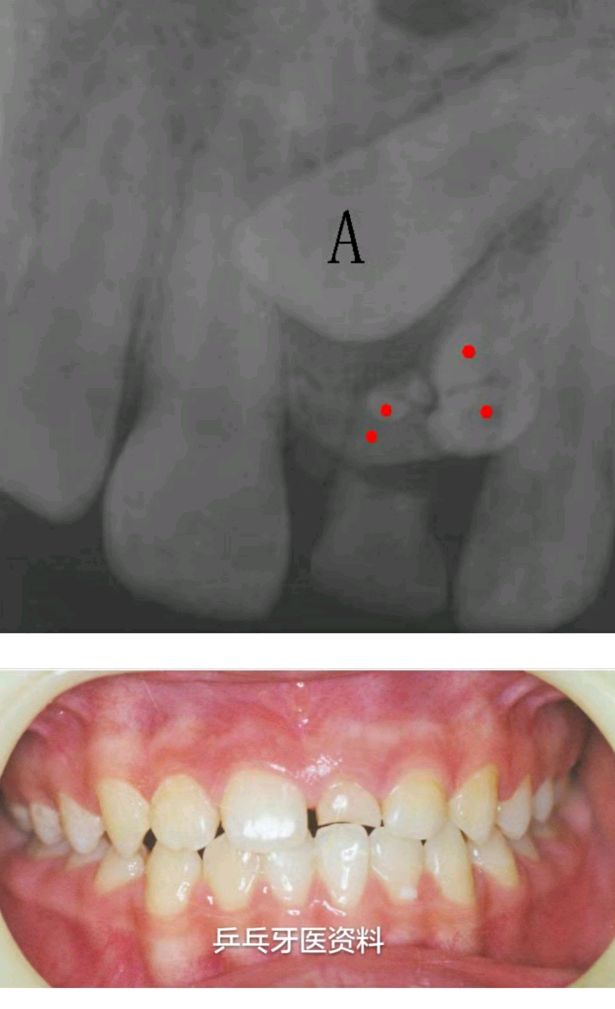

多生牙导致第二乳磨牙阻生